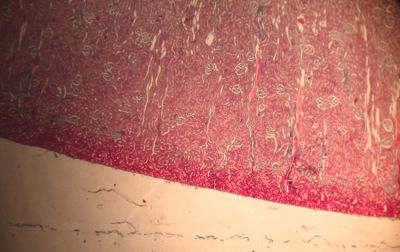

Kidney, rabbit - histology slide

This is a histology slide of a rabbit kidney.

Histology slide courtesy of Florida State University.